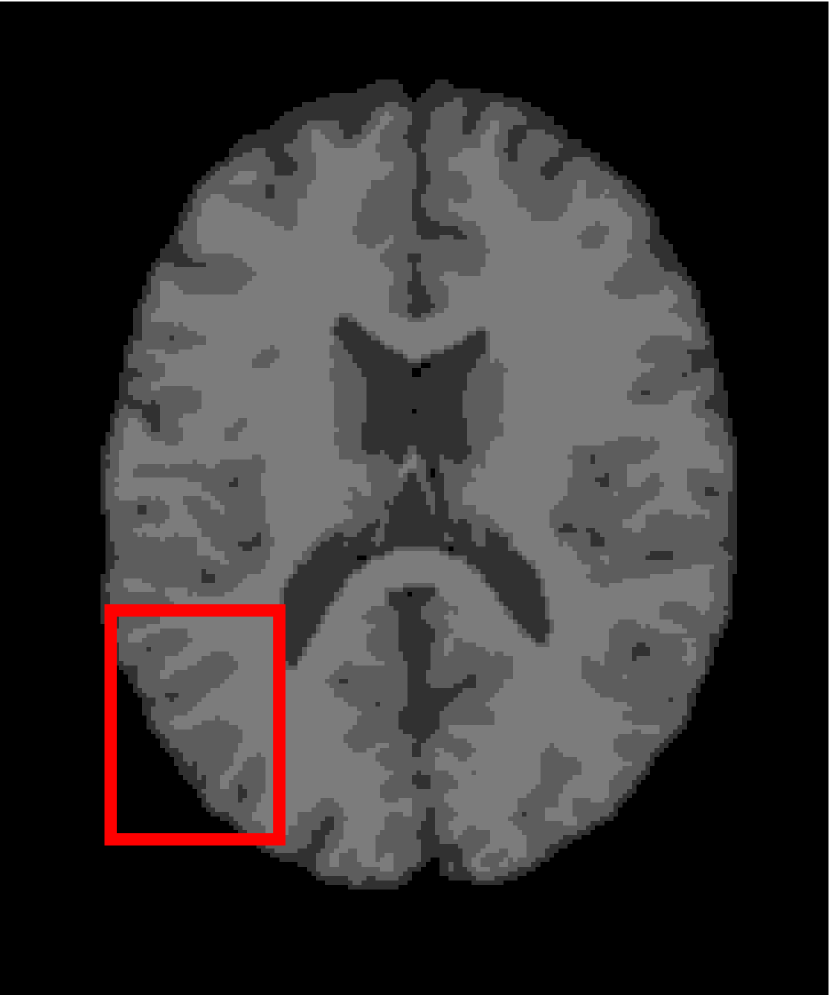

Next, we representatively segment five medical images from BrianWeb. They are represented as five slices in the axial plane with a sequence of 70, 80, 90, 100 and 110, which are generated by T1 modality with slice thickness of 1mm resolution, 9% noise and 20% intensity non-uniformity. Here, we set c=4𝑐4c=4 for all cases. The comparison between WRFCM and its peers are shown in Fig. 9 and Table II. The best values are in bold.

Figure 9: Segmentation results on five medical images. The parameter: ϕ=5.35italic-ϕ5.35\phi=5.35. From top to bottom: noisy images, ground truth, and results of FCM_S1, FCM_S2, FLICM, KWFLICM, FRFCM, WFCM, DSFCM_N, and WRFCM.

By a view of the marked red square in Fig. 9, we find that FCM_S1, FCM_S2, FLICM, KWFLICM and DSFCM_N are vulnerable to noise and intensity non-uniformity. They give rise to the change of topological shapes to some extent. Unlike them, FRFCM and WFCM achieve sufficient noise removal. However, they produce overly smooth contours. Compared with its seven peers, WRFCM can not only suppress noise adequately but also acquire accurate contours. Moreover, it yields the visual result closer to ground truth than its peers. As Table II shows, WRFCM obtains optimal SA, SDS and MCC results for all five medical images. As a conclusion, it outperforms its peers visually and quantitatively.